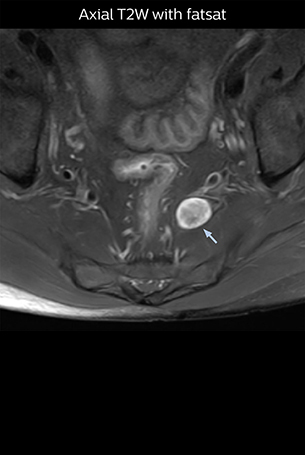

“Although symptoms of typical disc herniation and atypical hernia are very similar, the actual site of herniation is different. It is therefore important to characterize the nerve’s condition both inside and outside of the intervertebral foramina. “Conversely, if we see no abnormality in NerveVIEW, we can assume at least that there is no severe condition that requires surgery. Like this, it can help us avoid unnecessary surgery. NerveVIEW can have a tremendous impact in this way.”

“NerveVIEW is really useful for those cases where a nerve disorder is strongly suspected based on the clinical examination but our regular MRI images do not show any findings. These atypical herniations and spinal canal stenosis, occurring in 5% to 15% of the total lumbar herniation/stenosis cases are our main target when using NerveVIEW,” says Dr. Yabuki.

“The intra-luminal signal of veins, especially around the intervertebral space, can be suppressed well with NerveVIEW. As a result, we can easily observe the detailed nerve structure around the posterior ganglion,” he says. “This is why we use 3D NerveVIEW for intraforaminal stenosis and extraforaminal stenosis/herniation (lateral disc herniation). On the other hand, if herniation is suspected to exist inside the dorsal root ganglion (DRG), balanced TFE or ProSet-FFE is applied. NerveVIEW is not suitable for evaluating the median type of herniation.” The SE-EPI DWI-based method for MR neurography works well for large FOV exams like whole-body MRI, but focal examination of nerves is often limited by the attainable spatial resolution (both inplane and slice direction) and geometric distortion. “3D NerveVIEW achieves higher in-plane resolution – close to our other routine spine sequences – and the source images can be used instead of adding a fat-suppressed T2-weighted sequence,” Tanji says.